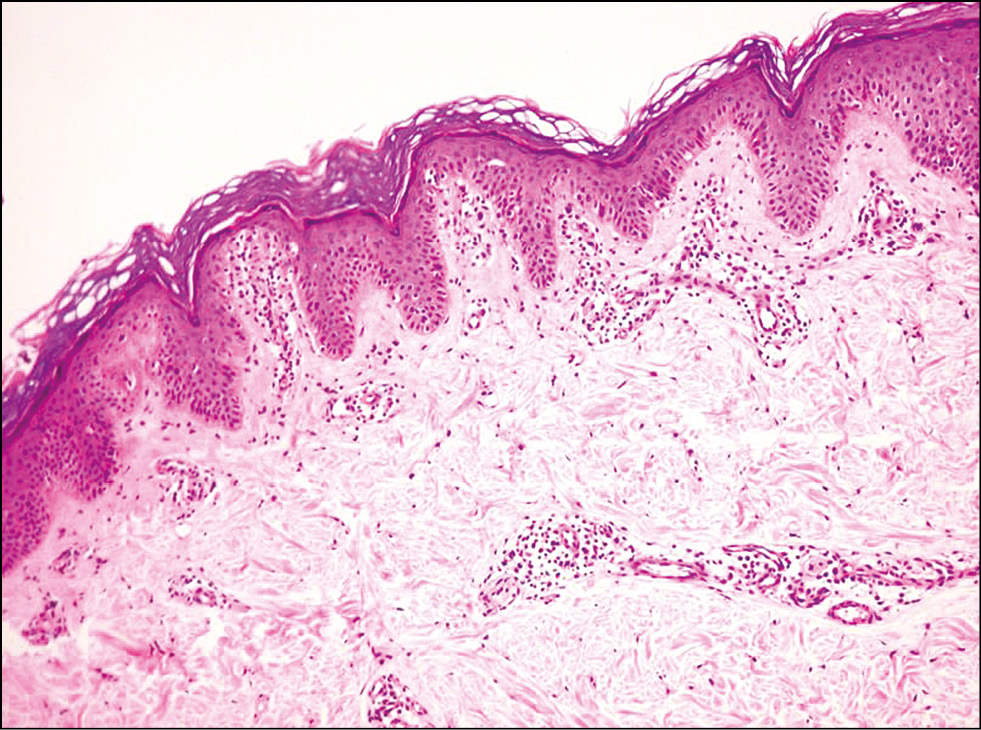

Четвёртую группу составили 10 пациентов с диагнозом «Крупнобляшечный парапсориаз», из них 5 женщин и 5 мужчин, средний возраст 59±8 лет. Гистологическое исследование у данной когорты показало наличие следующих признаков: поверхностный лихеноидный инфильтрат из мелких лимфоцитов, в некоторых случаях определялись клетки с атипичными ядрами, экзоцитоз, фокальная атрофия эпидермиса (рис. 9).

Рис. 9. Диагноз «Крупнобляшечный парапсориаз»: в эпидермисе отмечается ортокератоз, псориазиформный акантоз; в сосочковом слое дермы ― полосовидный инфильтрат, состоящий из атипичных лимфоцитов, с тенденцией к проникновению в эпидермис (эпидермотропизм). Окраска гематоксилином и эозином. ×100. / Fig. 9. The diagnosis is a large-plaque parapsoriasis. There is an ortokeratosis and psoriasiform acantosis of the epidermis. In the papillary dermis there is a lichenoid infiltrate of atypical lymphocytes with a tendency to penetrate the epidermis. (Hematoxylin & Eosin staining, ×100).